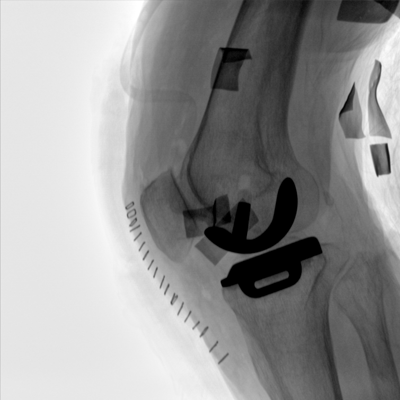

大尺寸動態平板探測器,高DQE、低噪聲、圖像清晰。采用多分辨率圖像增強處理技術,不同部位不同圖像處理算法,滿足客戶多樣化的需求。

圖形化操控界面設計:設有多種人體特征攝影參數,操作簡便。雙向紅光十字定位系統:實現無射線下的高效定位。信息共享:遵循DICOM3.0格式接口,可無縫對接云PACS系統。

多角度自由旋轉,滿足患者復雜擺位需求。